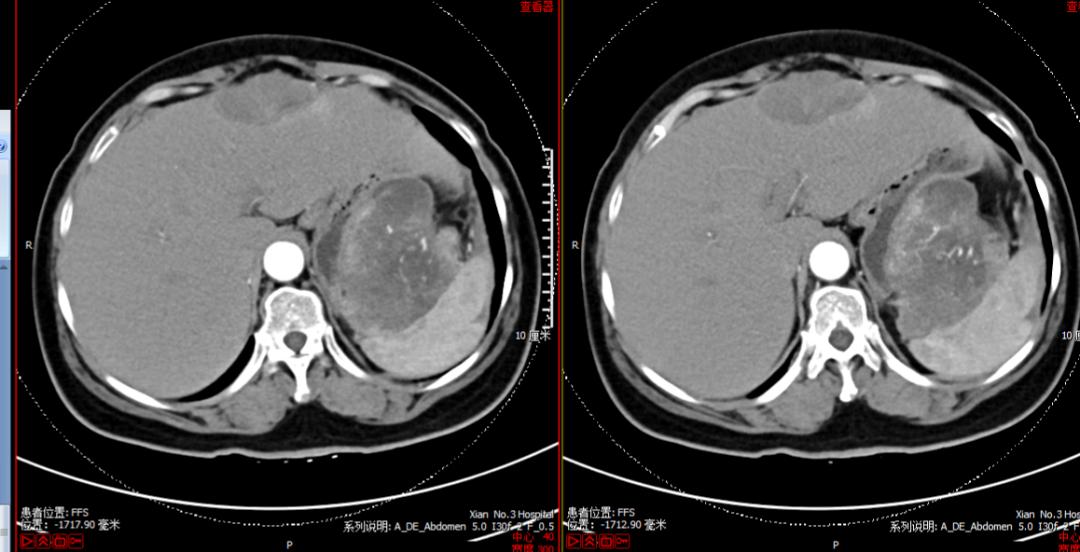

图2患者的腹腔及盆腔强化CT结果

我们的患者除了腹腔多发病灶外,已有肝脏转移,但无远处淋巴结转移,应该属于3期。